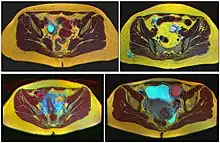

Four kinds of ovarian cysts on MRI

Ovarian cysts are usually diagnosed by ultrasound, CT scan, or MRI, and correlated with clinical presentation and endocrinologic tests as appropriate.[10]